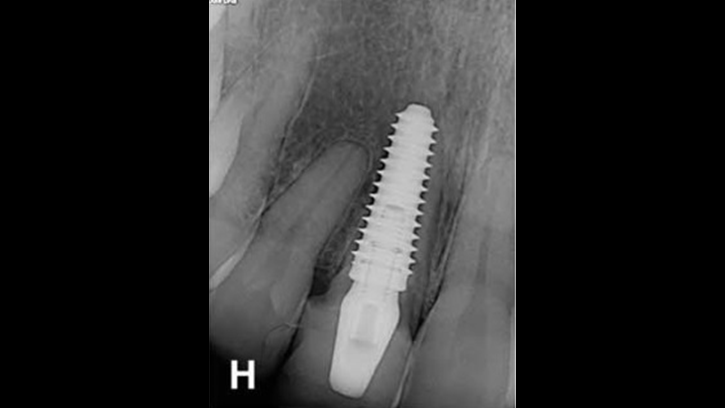

Clinical case: Bone growth in deepest thread of 8.0mm AnyRidge fixture

- Courtesy of Dr. Kwang Bum Park -

Clinical case: Bone filling into the bottom of deepest thread at 8.0mm AnyRidge fixture

Keywords

AnyRidge, Knifethread ,extraction socket, ,initial stability ,Allograft, ,osseointegratio ,Dr. Kwang Bum Park, , Mandibular, Single replacement, AnyRidge, Mega-oss,

Products used

Implant system-AnyRidge, Regeneration-Mega-Oss